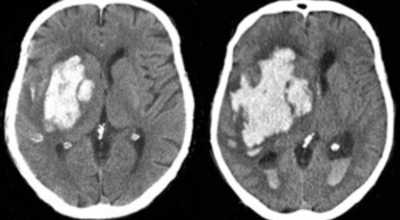

뇌출혈이란

뇌출혈이란 뇌혈관의 출혈이 원인이 되어 일어나는 뇌혈관장애, 뇌일혈이라고도 그러나, 이는 갑작스러운 의식 장애, 이완성 반신불수 등을 유발하는 뇌졸중을 유발하는 대표적인 질환이예요. 뇌출혈의 대부분의 원인은 고혈압증이 원인이지만 드물게 백혈병이나 재생불량성 빈혈 과 같은 혈액질환과 함께 종양, 외상, 매독 등이 원인이 됩니다.

고혈압성 뇌출혈의 원인은 고혈압만이 아니라 터지기 쉬운 상태의 혈관에도 있다고 생각이 가능하지만, 아직까지 발생병리는 완전히 해명이 되지 않은 상태예요. 현재 생각 되는 것은 뇌내세 소동맥, 보통과 다르게 분기부의 혈관벽에 변화가 일어나서 연약해진 곳이 내압을 이겨내지 못하고 팽배해서 터져서 출혈을 한다는 것이죠. 뇌출혈이 일어나는 장소는 내포 부근이 가장 많다고 하며 이 부분의 중대뇌동맥의 가지가 터져서 출혈해요.

뇌출혈의 원인은 아주 다양한것으로 알려져 있답니다. 그중에서 가장 가장 저명한 뇌출혈 까닭으로는 고혈압을 꼽을 수 있습니다. 뇌출혈 발생원인이 되는 약 70%를 차지하는 고혈압은 혈관내 압력이 높은채로 쭉되게되면 세동맥혈관이 괴사되어 미세동맥류가 되는데 이는 파열되어 뇌출혈을 발생시킬 수 있죠. 그리고 외부의 쇼크으로 인한 뇌출혈도 생기게 될 수 있다고 하며, 당뇨, 뇌동맥류, 뇌종용과 같은 다양한 원인이 있답니다.

뇌출혈은 발작 직후 안정을 취해야 해요. 뇌부기를 가라앉히기 위해 약물 요법으로 고농도 포도당, 덱사메타존, 만니톨 등을 투약할 수 있고 뇌의 혈액 순환을 회복시키는 주사와 지혈제, 진정제 등을 활용할 수 있답니다. 혈종의 크기가 중등도 이상으로 마비 증세가 있다면 머리뼈에 작은 구멍을 내서 관을 넣어 혈종을 뽑아내는 수술을 시행할 수 있습니다.

혈압성 뇌출혈인 경우 혈종의 크기가 작으며 환자의 증상이 경미하면 약물 치료를 시행해요. 혈종의 크기가 아주 크며 뇌가 심하게 부어오를 때는 응급으로 머리뼈를 절개해 혈종을 빠르게 제거해야해요. 응급조치가 늦어지면 뇌압이 상승해 의식을 잃고 사망에 이를 수 있기 때문인데요 이렇게 증상이 심할 때는 수술이 잘 되었더라도 예후가 좋지 못할 때가 많다고 해요.